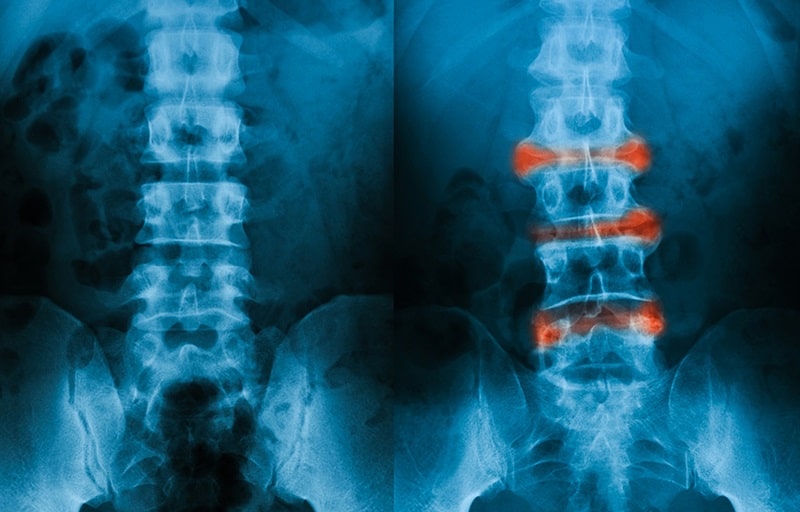

Dấu hiệu viêm cột sống dính khớp?

Dấu hiệu ban đầu của viêm cột sống dính khớp thường là đau cột sống thắt lưng, viêm các khớp chi dưới. Cơn đau sẽ tăng mạnh và rõ nhất là khi vào buổi sáng sớm lúc mà mọi người mới ngủ dậy.

– Khi bệnh chuyển sang giai đoạn nặng hơn, người bệnh sẽ đau thêm các vị trí như eo, lưng bị gù, cổ thường hay vươn về phía trước.

Viêm cột sống dính khớp có chữa được không?

Viêm cột sống dính khớp có chữa được không đang là thắc mắc của khá nhiều người. Theo các chuyên gia, bác sĩ viêm cột sống dính khớp là một bệnh lý mãn tính gây ra tổn thương nghiêm trọng cho cột sống và khớp xương hiện nay chưa có pháp điều trị khỏi hoàn toàn. Tuy nhiên, với sự phát triển của y học hiện nay, bệnh viêm cột sống dính khớp vẫn có thể được giảm đau và cải thiện kể chất lượng sống cho người bệnh.